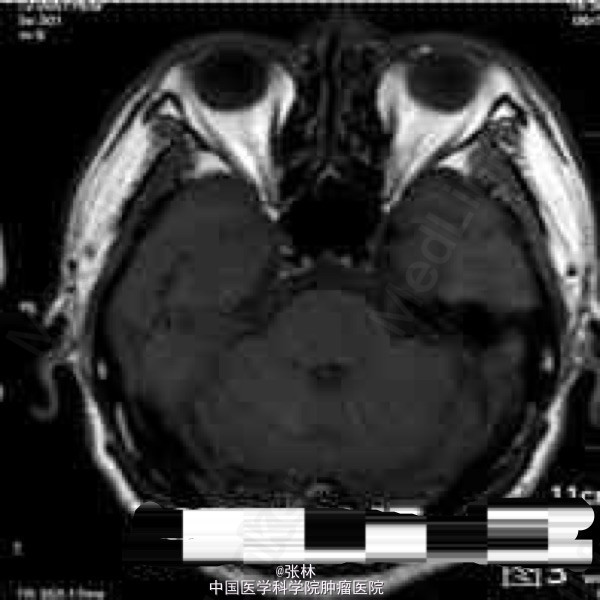

CT表现:右侧颅中窝可见一不规则肿块,呈等密度,内部密度均匀,CT值约37HU,肿块边界尚清晰,略成分叶状,与邻近骨质呈广基底相连,最大截面3.3cm×3.8cm,边缘处可见带状低密度影,边界清晰,CT值约16HU。肿块周边脑组织水肿,密度略减低。肿块周边骨质未见增厚硬化或变薄等异常改变(图1-2)。 CT诊断:右侧颅中窝肿块,伴周围脑组织水肿,建议进一步检查。 MRI表现:右侧颅中窝可见一不规则肿块,最大截面3.6cm×4.1cm,肿块边界清晰,成分叶状,与邻近骨质呈广基底相连(图5-6),在T1WI上呈等信号,在T2WI上呈略高信号;肿块边缘可见不规则液性信号带,在T1WI上呈低信号,在T2WI上呈高信号,与脑组织分界清楚(图3-4);肿块前方颞叶部分脑组织可见片状异常信号,在T1WI上呈稍低信号,在T2WI上呈略高信号,边缘模糊(图3-4);注射对比剂后,肿块实性部分明显强化,并可见“脑膜尾征”,而液性信号带未见强化(图5-6),肿块前方颞叶的片状异常信号未见强化。 MRI诊断:右侧颅中窝脑膜瘤,部分囊变,伴周围脑组织水肿。 手术病理结果:非典型性脑膜瘤,WHO分级II级。 讨论: 脑膜瘤是颅内仅次于胶质瘤的常见原发肿瘤,发病率占颅内肿瘤的16%~17%,在颅内脑外原发肿瘤中占第一位。它起源于脑膜的蛛网膜内皮细胞,常见于富含蛛网膜颗粒与蛛网膜绒毛的地方,以上矢状窦旁、大脑凸面、大脑镰、蝶骨嵴、鞍结节、嗅沟、小脑桥脑角区及小脑幕等部位多见。